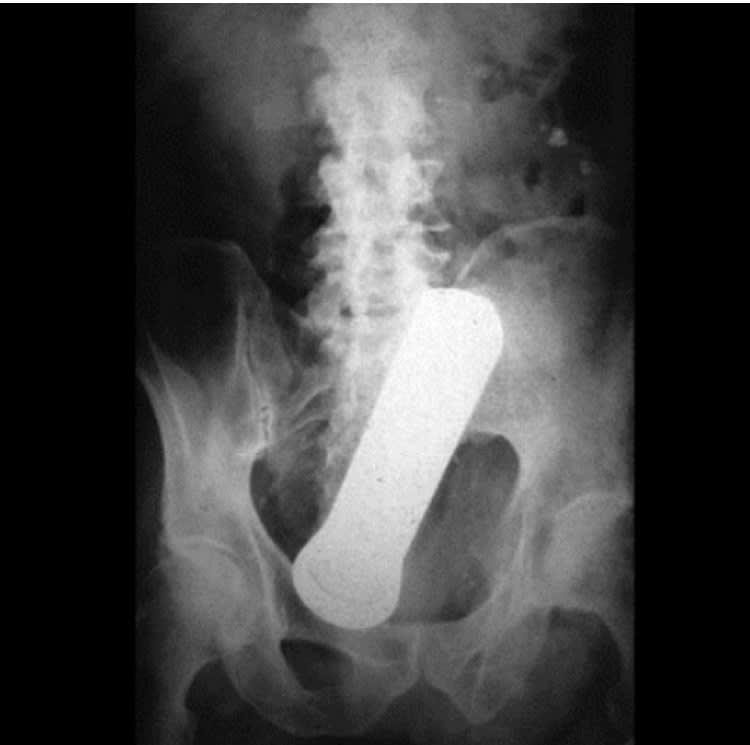

Petit jeu : le premier qui a trouvé l'ensemble des éléments coincés , a gagné 😊